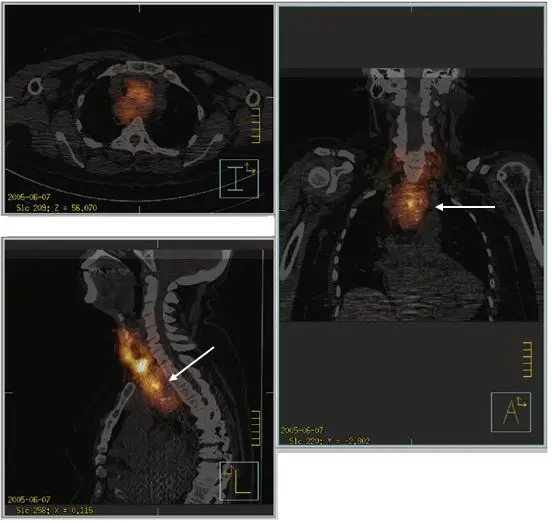

¹²³I-NaI甲狀腺之單光子電腦斷層造影與電腦斷層融合影像(如下圖),箭頭所指最可能為何?(圖I:橫向面影像,圖L:縱向面影像,圖A:冠狀面影像)

本題提供三張 I-NaI 甲狀腺 SPECT/CT 融合影像,可分別觀察放射性同位素攝取的位置:

- 圖I(橫向面影像,Transaxial view,左上圖):影像顯示放射性碘的高攝取區位於胸腔中央,被兩側低密度的肺野包圍,解剖位置屬於縱膈腔。

- 圖L(縱向面/矢狀面影像,Sagittal view,左下圖):箭頭指向一巨大且呈高放射性攝取的組織。從側面解剖構造可清楚看出,該組織位於胸骨(Sternum)後方、氣管與脊椎的前方,並從頸部下端一路向下延伸進入胸腔內(低於胸廓入口),此位置為前上縱膈腔。

- 圖A(冠狀面影像,Coronal view,右圖):箭頭同樣指向該高攝取病灶,其位置明顯低於正常頸部甲狀腺的所在高度,落於兩側肺部之間的上縱膈